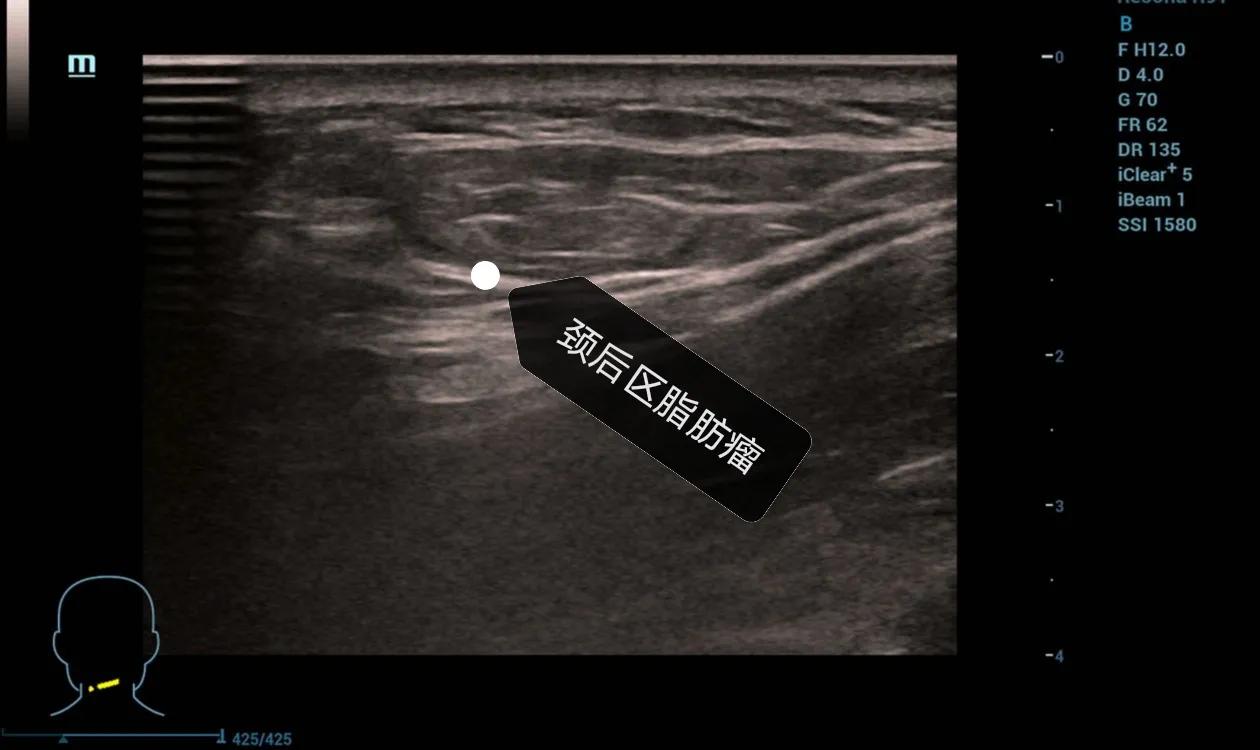

此外还有一个名词大家或许听得比较多,“富贵包”,有些人,尤其是肥胖的人脖子后边凸起一个包块,其实本质上就是异常的脂肪堆积,也是脂肪瘤。

下面给大家分享几个我平时做的病例,发生在各个部位的脂肪瘤。

高回声的脂肪瘤